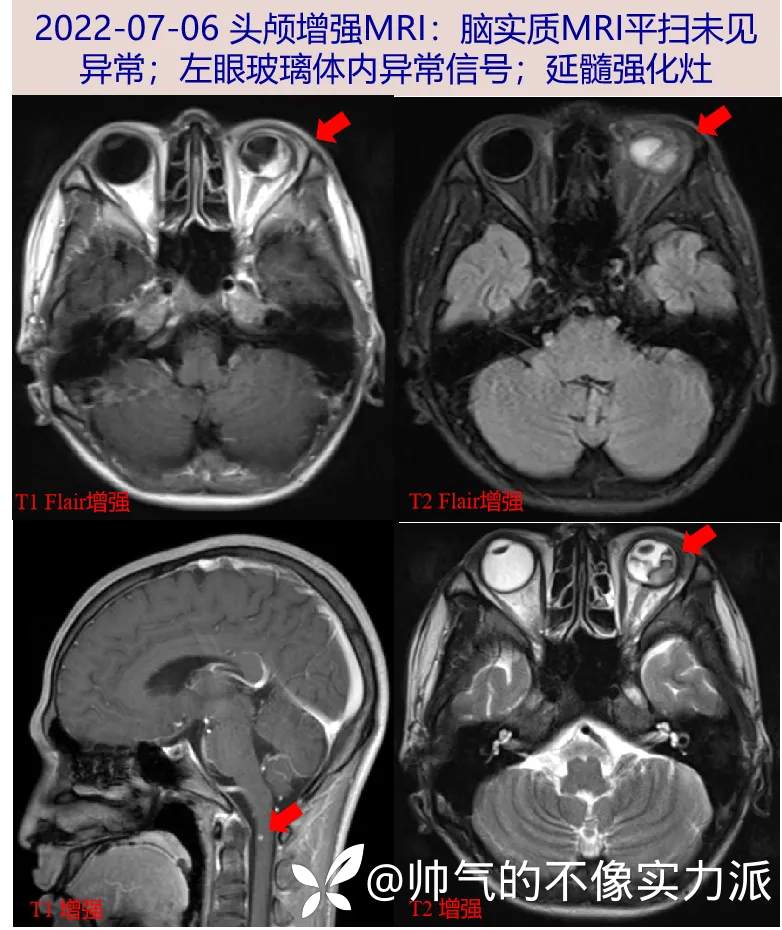

- 2022-07-06 完善头颅增强MRI:脑实质未见异常;左眼玻璃体内异常信号;延髓强化灶。神经内科会诊考虑延髓病变待查,予加用维生素B1、B12各1支qd肌注,必要时完善腰椎穿刺。